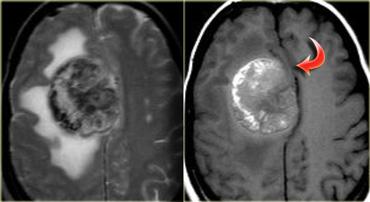

Ngấm thuốc dạng vòng

Ngấm thuốc dạng vòng được thấy trong di căn não và u thần kinh đệm độ cao.

Nó cũng được thấy trong các tổn thương không phải u như áp xe, một số mảng xơ cứng rải rác (MS) và đôi khi trong khối máu tụ cũ.

Bên trái là ba tổn thương ngấm thuốc dạng vòng khác nhau.